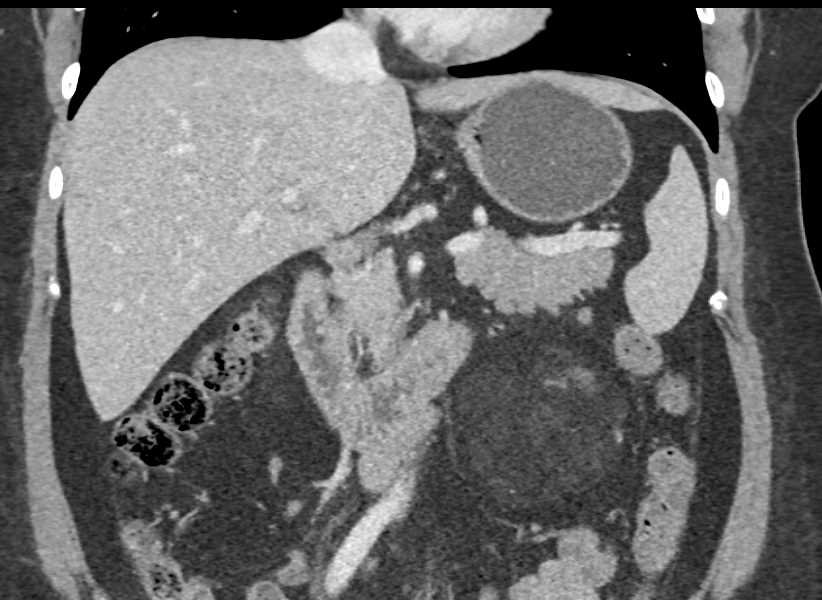

КТ ретроперитонеального фиброза: Изображения и диагностика

Раздел: Мудрость в деталях